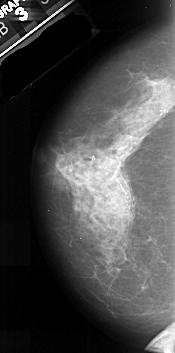

A_1035_1.LEFT_CC

LEFT_CC LINES 4936 PIXELS_PER_LINE 2446 BITS_PER_PIXEL 16 RESOLUTION 42 NON_OVERLAY